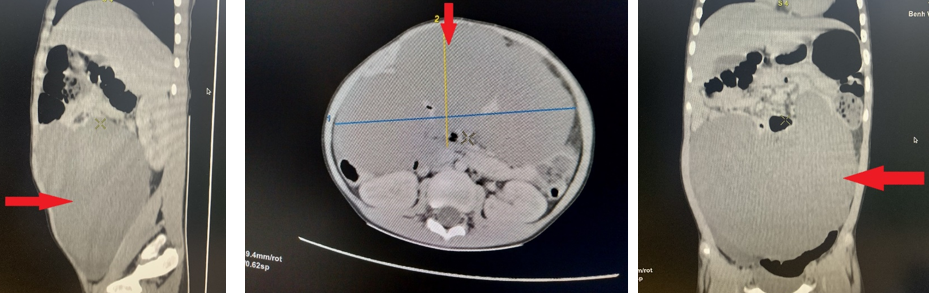

CT –

Scanner bụng Hình ảnh khối u lớn kích thước

~170 x 94 x 123 mm chiếm hầu hết ổ bụng gây đè đẩy các tạng xung quanh